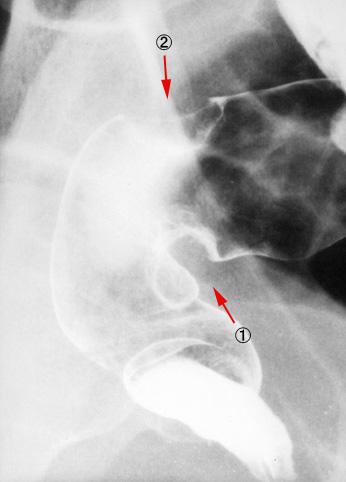

사다리꼴 변형과 호상 변형을 나타낸 2개의 대장암병변을 가진 예

[Image-ID:8983]

악성 상피성종양/선암

대장/직장

X-P

2형(궤양국한형)/

25~29

mp

다발종양(동일 장기)

유(동시성)